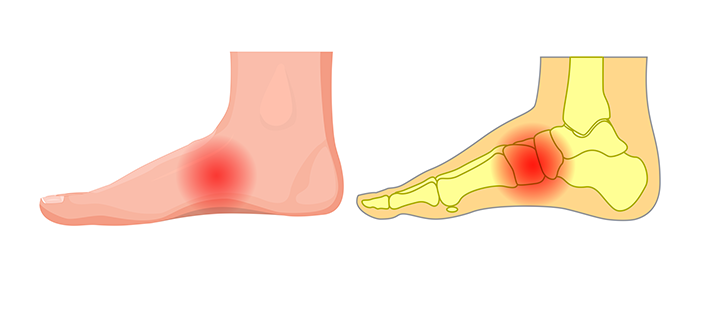

Before we get into the cause of pain in the arch of the foot, let’s quickly cover some anatomy to make sure you’re identifying the right concern. The arch of the foot is in between the toes and the heel, in the area that is naturally elevated from the ground in an arch shape. It is made up of three separate arches - made from tarsal and metatarsal bones, ligaments and tendons - that form a triangle arched up away from the ground.

The arch acts similarly to a spring: it upholds the weight of the body while absorbing the shock of the body against the hard surface of the ground. The flexible and durable structure of the feet allow the vast range of movement of humans; from jumping to sprinting to changing direction.

But there are issues that come with this design: a high arch or flat feet can cause problems. This may manifest as pain in the arch of the foot or secondary issues like ankle pain, tight hips, back pain, or issues while in motion.